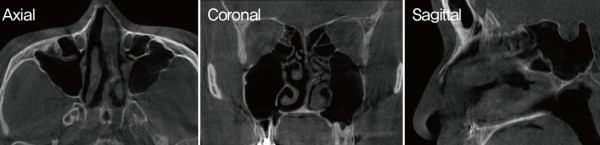

![]()

수술 전 비내시경. 비중격이 전체적으로 좌측으로 만곡되어 C-shape

deviation이 확인되었다. 미단부 변형으로 인해 좌측 비밸브 협착이 보였다.

비중격 만곡은 CT보다 내시경상에서 더 심하게 나타났다

내시경 검사에서는 CT에서보다 더 심한 비중격 만곡이 관찰되었으며, 비밸브 협 착이 보여 비중격 및 비밸브 교정술,

하 비갑개 점막 절제술을 계획하였다.